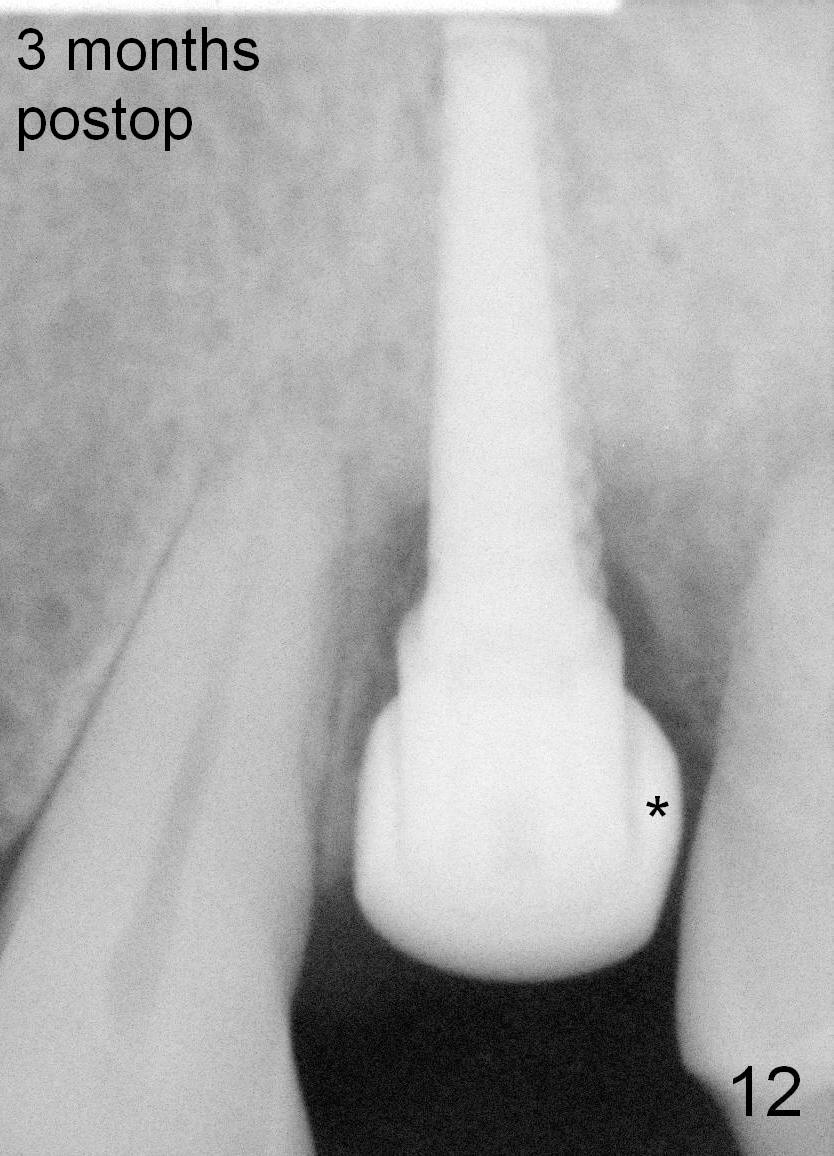

Fig.3,7,10-14 (at the same magnification) show regrowth of crestal bone around the implant postop.

Fig.13,14: *: crestal bone.